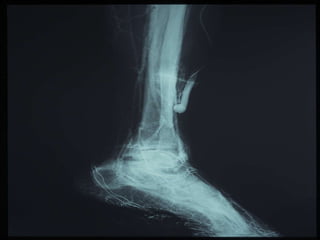

O PÉ DIABÉTICO E SUAS ESPECIFICIDADES   VASCULOPATIA DIABÉTICA   ALTERAÇÕES DA MICROCIRCULAÇÃO CUTÂNEA ATEROSCLEROSE DAS EXTREMIDADES INFERIORES  (calcificações parietais e predomínio de doença femoro popliteia e distal) FUNÇÃO IMUNE CITOMEDIADA ESTÁ ALTERADA  -  MAIOR RISCO DE COLONIZAÇÃO E INFECÇÃO BACTERIANA

O PÉ DIABÉTICOE SUAS ESPECIFICIDADES VASCULOPATIA DIABÉTICA ALTERAÇÕES DA MICROCIRCULAÇÃO CUTÂNEA ATEROSCLEROSE DAS EXTREMIDADES INFERIORES (calcificações parietais e predomínio de doença femoro popliteia e distal) FUNÇÃO IMUNE CITOMEDIADA ESTÁ ALTERADA - MAIOR RISCO DE COLONIZAÇÃO E INFECÇÃO BACTERIANA

ISQUÉMIA CRÍTICA Recommendation 73 CLINICAL DEFINITION OF CRITICAL LIMB ISQUEMIA The term critical limb ischemia should be used for all patients with chronic ischemic rest pain, ulcers, or gangrene attributable to objectively proven arterial occlusive disease. The term critical limb ischemia implies chronicity and is to be distinguished from acute limb ischemia.  TASC Working Group

ISQUÉMIA CRÍTICA Recommendation73 CLINICAL DEFINITION OF CRITICAL LIMB ISQUEMIA The term critical limb ischemia should be used for all patients with chronic ischemic rest pain, ulcers, or gangrene attributable to objectively proven arterial occlusive disease. The term critical limb ischemia implies chronicity and is to be distinguished from acute limb ischemia. TASC Working Group